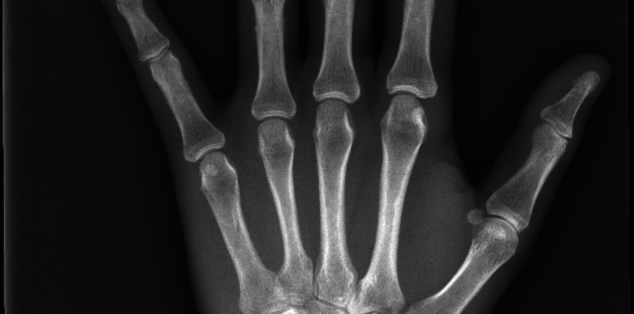

Emily, Fractured 5th Metacarpal

On March 19 I was about 15 miles in on the 50k race known as HAT. There was a large rock on the trail and I utilized my left hand to attempt to break my fall. I got back up and kept running. The next day I had severe pain and increased swelling. I went to morning breakfast with my running club and the foot doctor told me to get it x-rayed. I went to a prompt care in DE and x-ray revealed a spiral fracture of the 5th metacarpal on my left hand. I was devastated and in shock. I'm an ultra runner and for me being told by that doctor that I couldn't run my upcoming race was like being told you can't breathe.